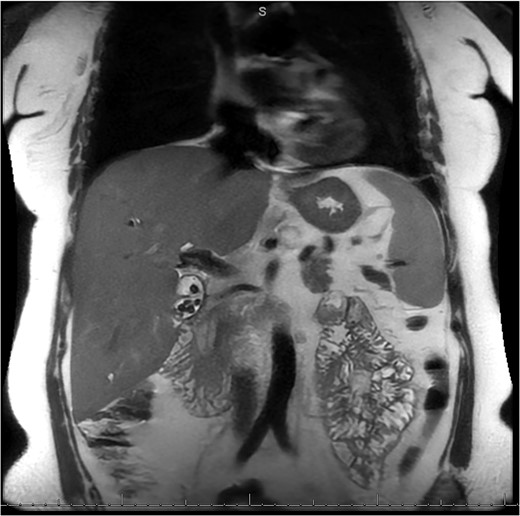

MRI/MRCP from second hospitalization demonstrating liver and kidney cysts.

A 49-year-old female with a history of ADPKD and multiple liver cysts, 13-months status post subtotal cholecystectomy, endoscopic retrograde cholangiopancreatography with biliary sphincterotomy and balloon stone extraction, presented to the emergency department with fever and a 4-day history of discomfort in the right upper quadrant. At the time of the initial cholecystectomy, total cholecystectomy could not be performed due to extensive adhesions, and subtotal cholecystectomy with complete evacuation of the stones was done instead. Magnetic resonance cholangiopancreatography (MRCP) done at that time showed a dilated common bile duct (CBD) to 1.5 cm, intra and extrahepatic biliary dilatation, multiple liver cysts measuring up to 2 cm, and multiple stones in the CBD, including at the level of the ampulla (Fig. 1). Computerized tomography scan at the time of the second admission showed acute cholecystitis and she had mildly elevated transaminases, but there was no evidence of cholestasis or pancreatitis. MRCP showed minor proximal intrahepatic biliary dilation and cholelithiasis but no duct calculi (Figs 2–4). A laparoscopic cholecystectomy was attempted with extensive adhesiolysis between the gallbladder and surrounding omentum and mesocolon, but the cystic duct could not be isolated, and ultimately the cased was converted to open. While removing the gallbladder in a top-down fashion, a small bile leak was identified right at the closed end of the gallbladder remnant, where the bile duct was adhered to the gallbladder wall. Intraoperative cholangiogram was obtained through a small perforation in a right posterior bile duct at the site of attachment, which showed right posterior, right anterior and left hepatic ducts of equal size converged at a trifurcation (Fig. 5). The duct was repaired over a T-tube and observed throughout the rest of the case and no bile leak was identified. The gallbladder was opened along its lateral edge, revealing a hugely dilated cystic duct with ~10 to 12 marble-sized stones packed within the gallbladder remnant and cystic duct down to the juncture with the common bile duct. All the stones were removed and the safe portion of the gallbladder remnant was resected leaving the side attached to the bile duct in situ due to the Mirizzi anatomical variant. The cystic duct was oversewn along with the remnant of the gallbladder wall. Pathology showed acute-on-chronic cholecystitis with cholelithiasis. Repeat MRCP showed no retained stones in the biliary tree. The recovery course was unremarkable.